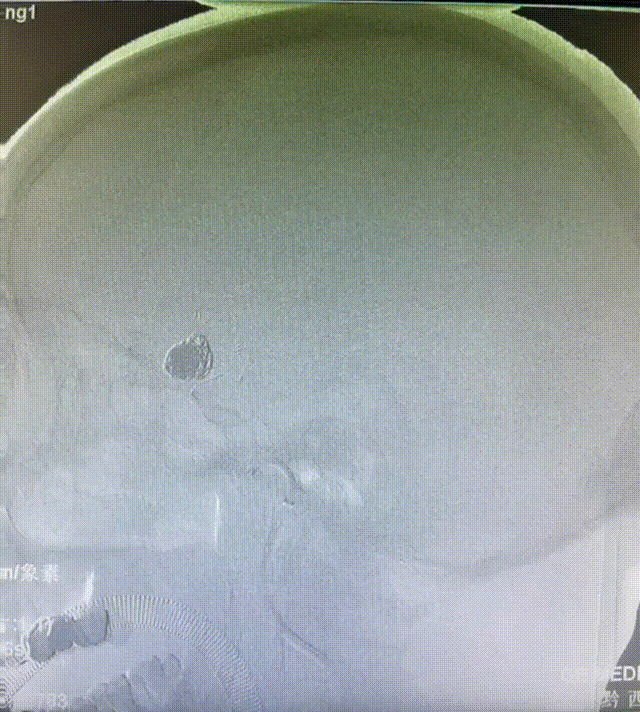

填塞第一个成篮圈:通桥凤®弹簧圈AEC-12-40-S,半释放EP2支架。

术后造影:弹簧圈致密填塞。

栓塞后造影:动脉瘤致密填塞。